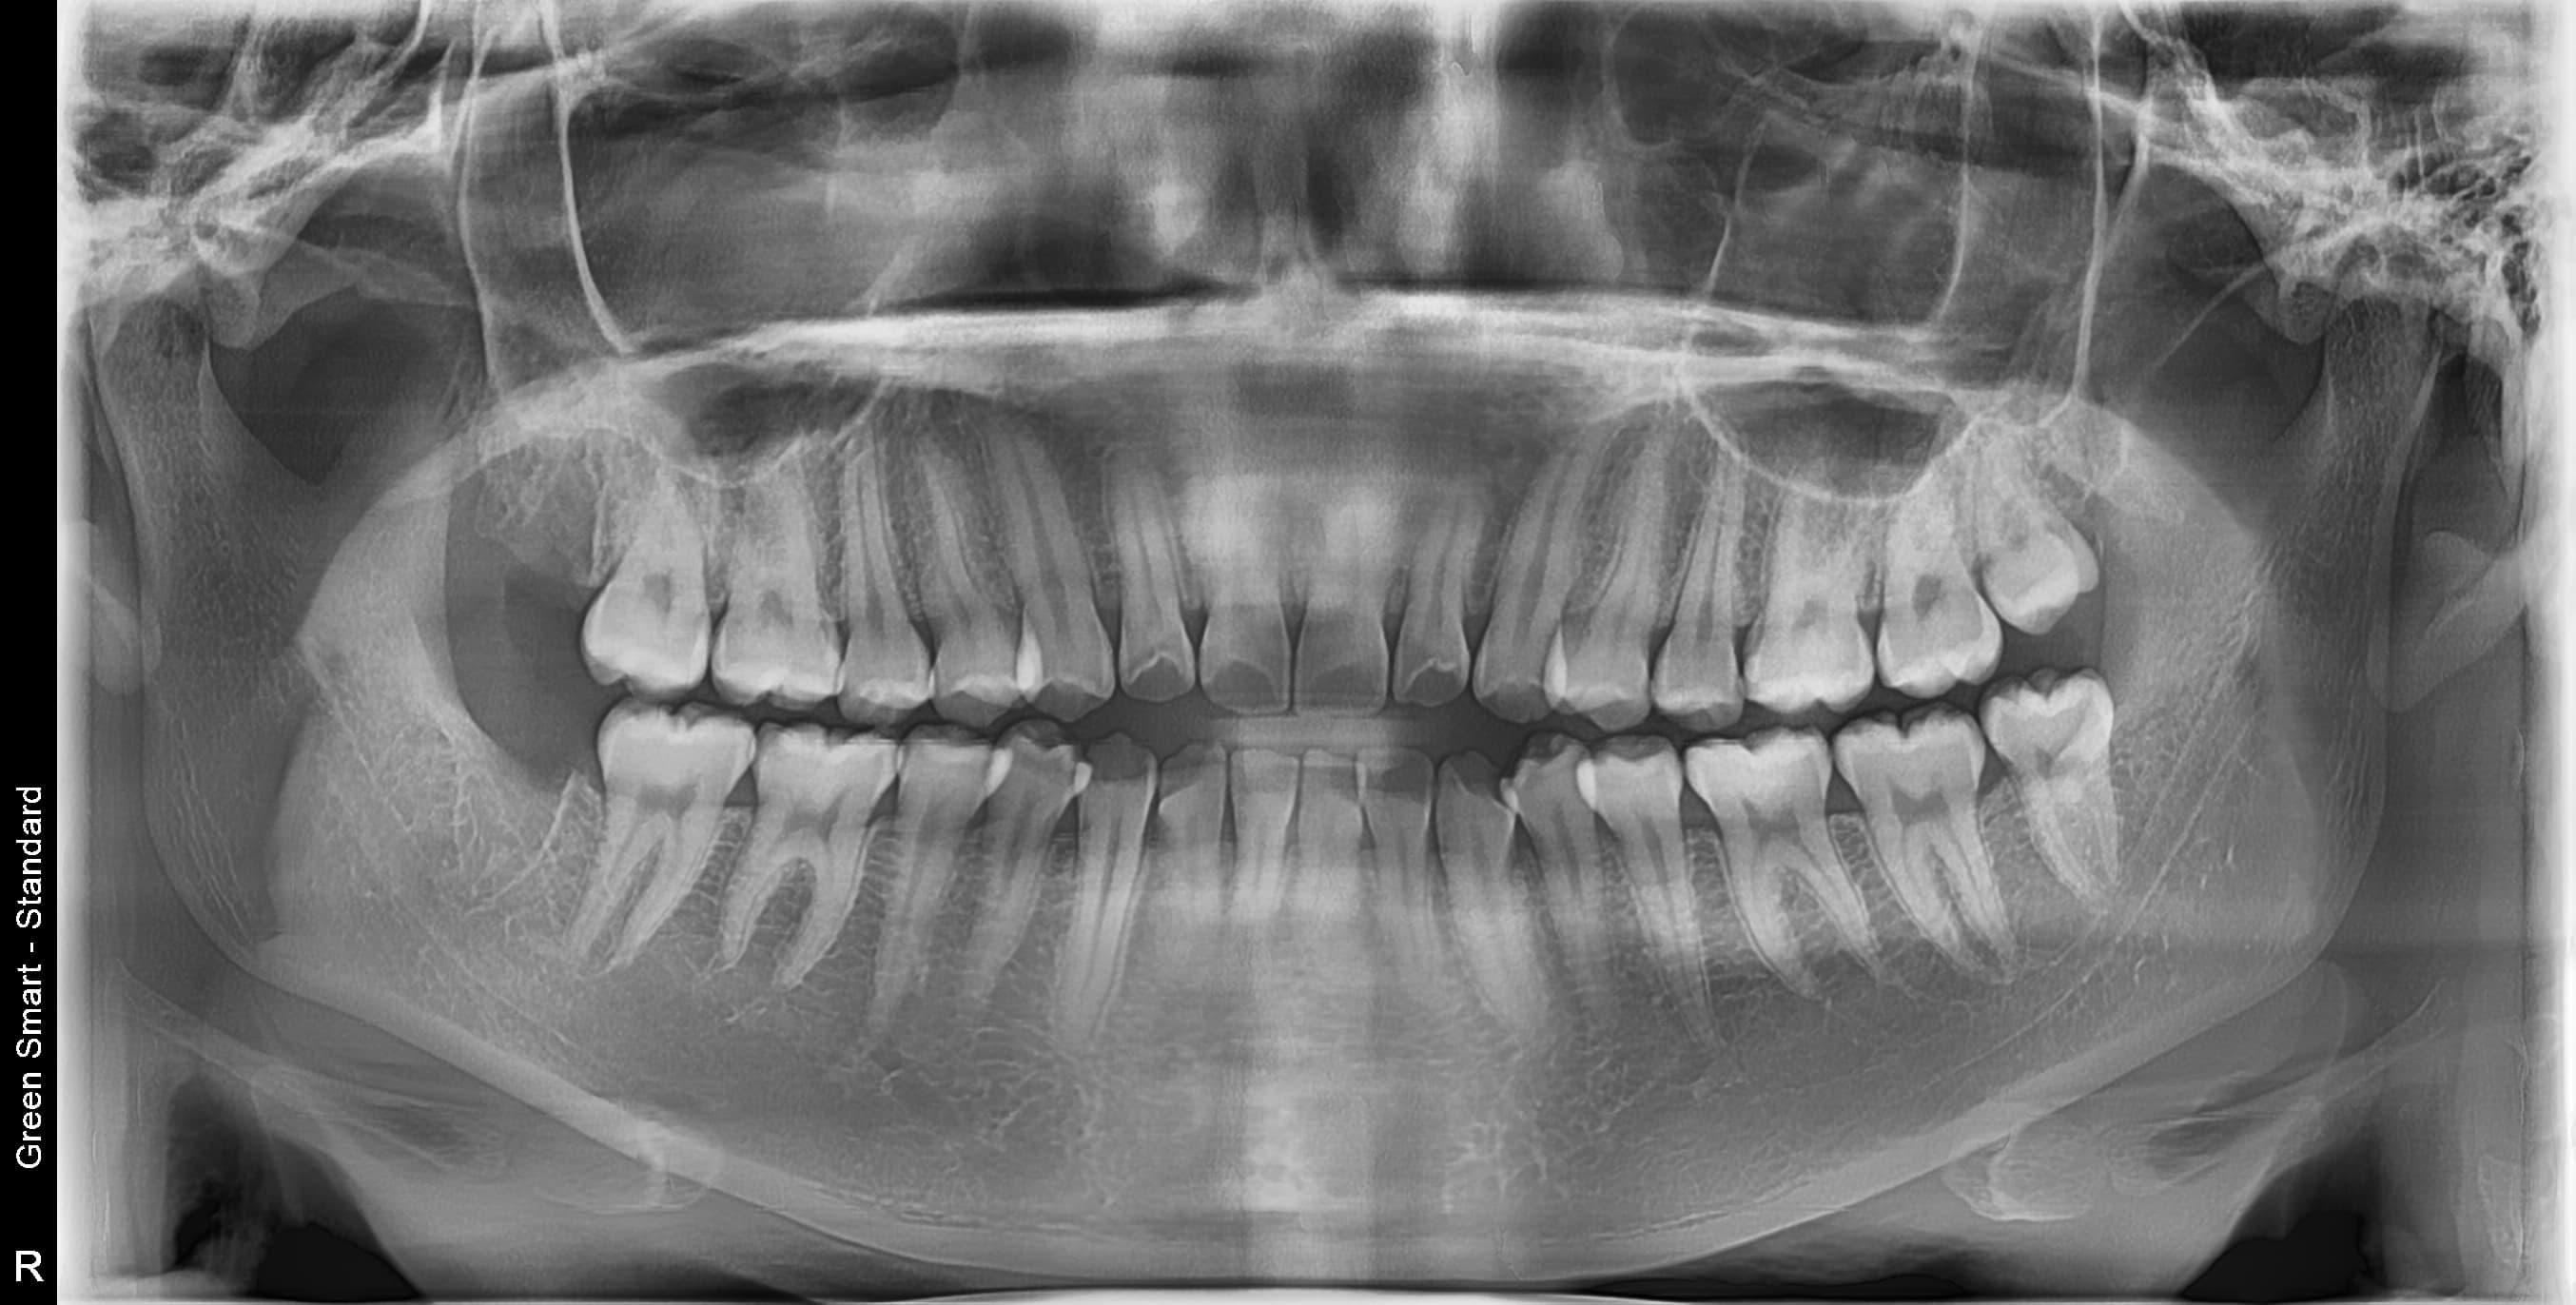

사랑니 상태별 위험도

Before

After

저위험

정상 사랑니

정상적으로 자란 사랑니도 관리가 어려워 충치 위험이 높습니다

중위험

부분매복 사랑니

음식물이 끼기 쉽고 염증이 자주 발생합니다

고위험

완전매복 사랑니

낭종 형성 가능성이 있어 조기 발치가 필요합니다

치근만곡 사랑니

뿌리가 구부러져 있어 발치 난이도가 높습니다

즉시 처치 필요

수평매복 사랑니

앞 치아를 밀어 치열 불균형과 충치를 유발합니다